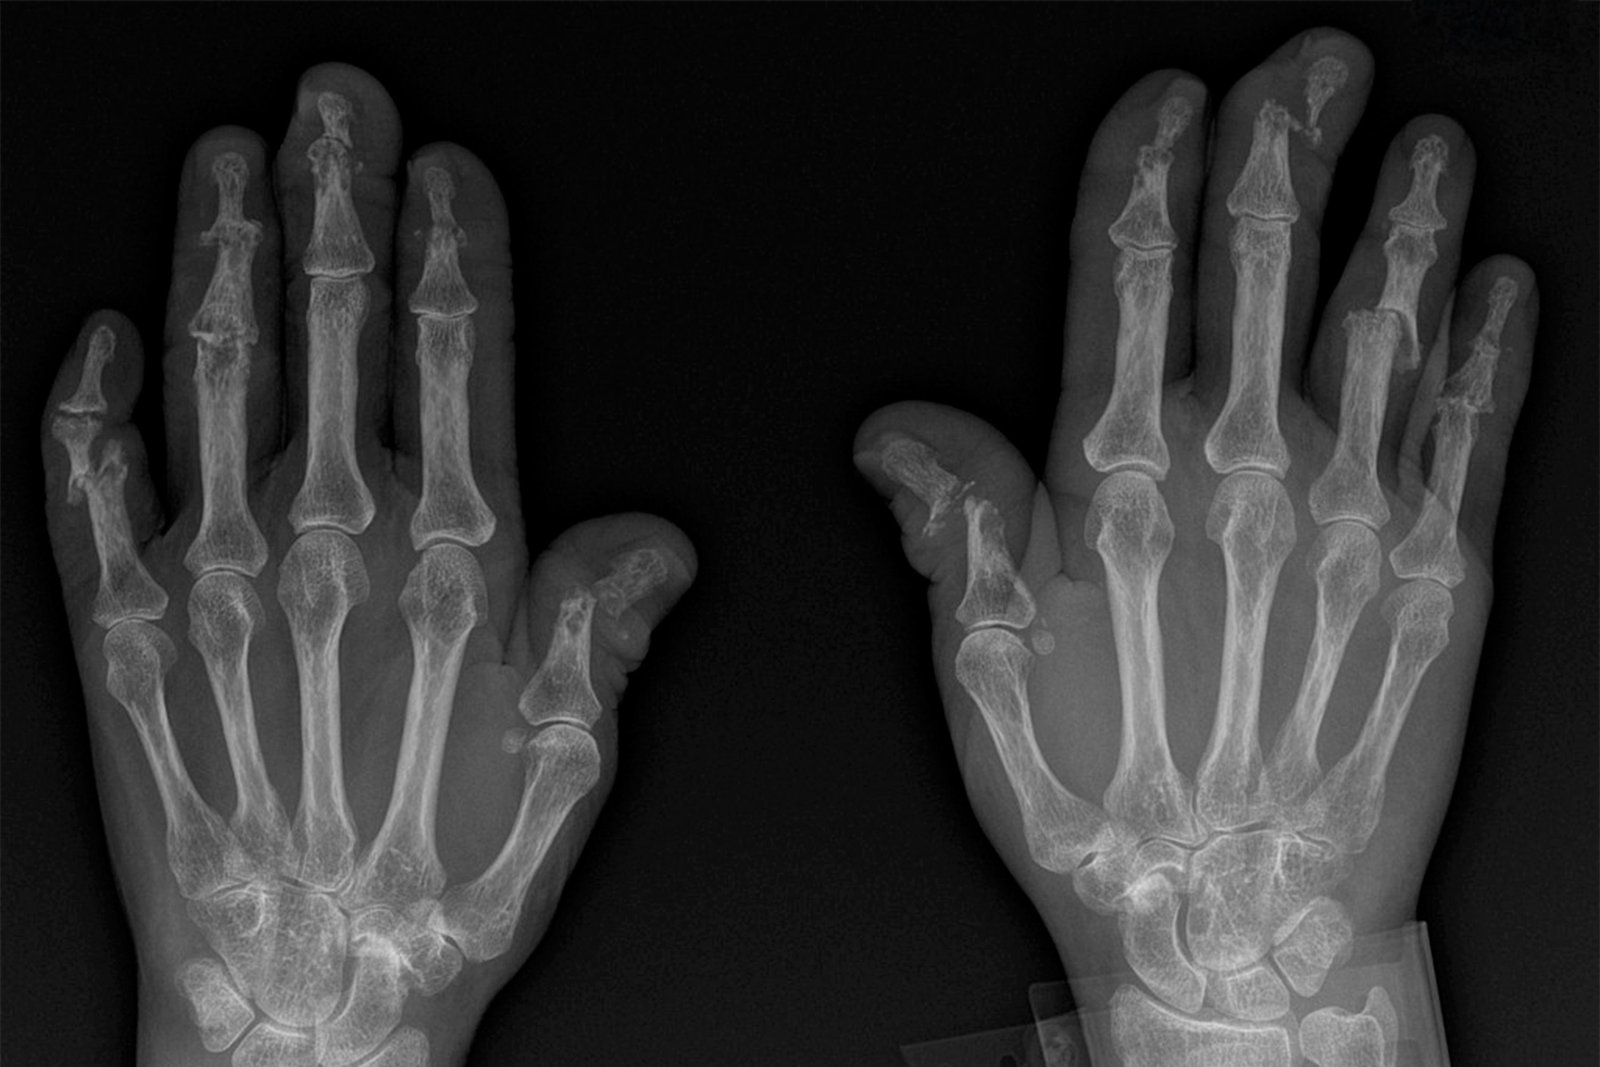

Arthritis Management

1. Arthritis is swelling and pain at one or more joints.

2. At SOH we provide comprehensive management of arthritis which includes

3. Early diagnosis of different types of arthritis.

4. Optimal medical management.

5. Prevention of pain and joint deformity and maintaining joint mobility by effective physiotherapy.

6. Surgical intervention in end stage disease in form of arthrodesis or joint replacement.